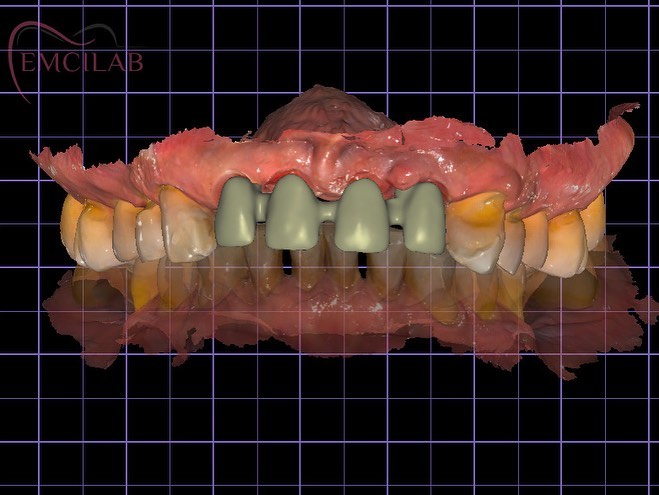

Emcilab Laboratorio Dental

Donde la precisión y la estética se fusionan para crear nuevas sonrisas….

Excelencia & Maestría, Complemento Ideal…

Soluciones avanzadas en restauraciones dentales para la odontología.

Soluciones avanzadas en restauraciones dentales para la odontología.